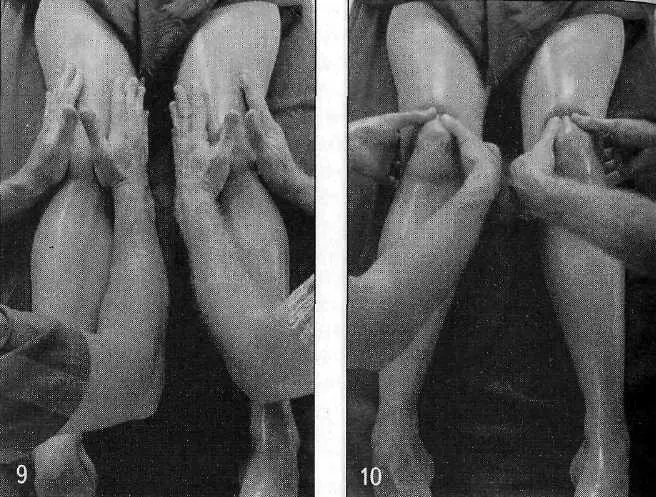

Бахья снехана представляет собой последовательность массажных движений, выполняемых в следующих направлениях: от пупка к голове, от головы к пупку, от пупка к ногам и от ног к пупку — на передней и задней поверхностях тела. Давление, прилагаемое массажистом, различается в зависимости от массируемой области (присутствия точек мармы). Согласно аюрведе, в точках мармы происходит соединение между физической материей тела и его внутренней мудростью. Стимуляция мармы оживляет и координирует взаимодействие субдош ваты, а следовательно, гармонизирует все нейрофизиологические процессы в организме.

По сравнению с башпа, нади представляет собой более проникающую разновидность воздействия, так как пар загоняет тепло и масло от бахья снеханы глубоко в ткани через поры кожи. Хотя применять нади сведану можно на всей поверхности тела, особое внимание уделяется крупным и сложным суставам для улучшения их подвижности. Обычная продолжительность процедуры составляет 5–7 минут. Безотносительно панчакармы, ее можно использовать в сочетании со снеханой для избавления от боли, мышечных спазмов и ригидности в конкретных областях тела, особенно — конечностей. Такое лечение хорошо успокаивает боли в спине при миозите и радикулите, в тазобедренных и коленных суставах.